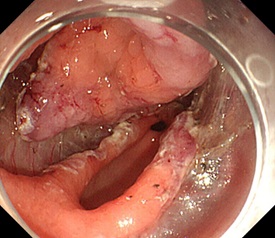

ESD

胃前庭部の半周程度を占める大きな拡がりの早期胃癌に対して行った、内視鏡的粘膜下層剥離術